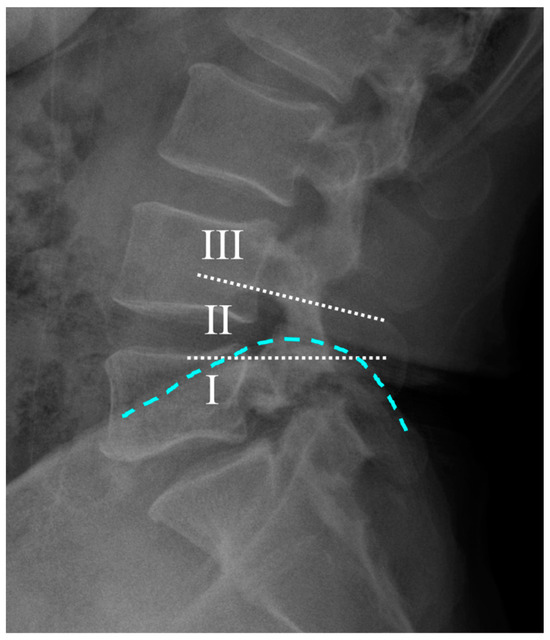

This cohort study was approved by the institutional review board (IRB no. 2024AN0319; date of approval: 28 June 2024). Patient consent was waived due to the retrospective nature of the study. The study included patients who underwent single-level OLIF surgery at the L4–5 level for degenerative spinal stenosis between March 2019 and April 2022. All operations were performed by our senior author (J.H.Y.). Patients who received surgery for other conditions, such as infection, trauma, or tumors, and those with incomplete medical records were excluded. Only patients who had a minimum follow-up of 2 years, during which both patient questionnaires and radiological evaluations were completed, were included in the study. The remaining patients were categorized into three groups based on the height of the iliac crest relative to the L4 and L5 pedicles, as observed on plain lateral radiographs (Figure 1). The grading system for the iliac crest height was adapted from the method proposed by Song et al., which was validated in a previous study [9]. Groups I, II, and III represented different grades of iliac crest height. For each patient, demographic variables, including age, sex, height, weight, and comorbidities, were recorded.

Radiological assessments included a comprehensive evaluation using plain radiography and computed tomography (CT). Lumbar lordosis and L4–5 segmental angles were measured on plain radiographs, and the presence of isthmic spondylolisthesis was assessed. The iliac crest was categorized based on its height on lumbar lateral plane radiographs (I, iliac crest below the L5 pedicle; II, iliac crest between the L4 and L5 pedicles; III, iliac crest above the L4 pedicle). Additionally, the relationship between the iliac crest height and the L4–5 disc level was quantified by measuring the distance from the midpoint of the L4–5 disc to the line connecting the ends of the iliac crest on lumbar AP radiographs.

Figure 1. Method of categorizing crest levels into three groups based on the relationship between the height of the iliac crest (light blue dotted line) and the L4 and L5 pedicles on lumbar lateral radiographs. The white dotted lines represent the lower edge of the L4 pedicle and the upper edge of the L5 pedicle. I represents the iliac crest height below the upper edge of the L5 pedicle; II indicates the iliac crest height between the lower edge of the L4 pedicle and the upper edge of the L5 pedicle; and III represents the iliac crest height above the lower edge of the L4 pedicle.